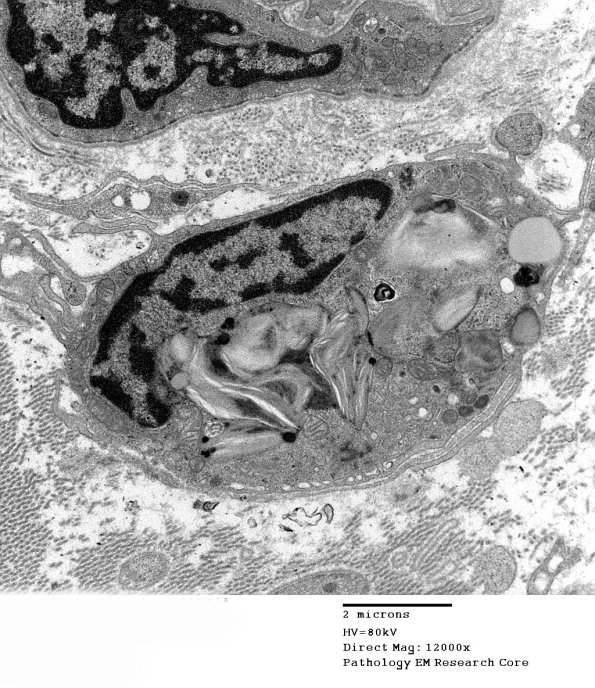

8A1,2 In this case variably dense Pi granules are present within a macrophage. (Electron micrographs)